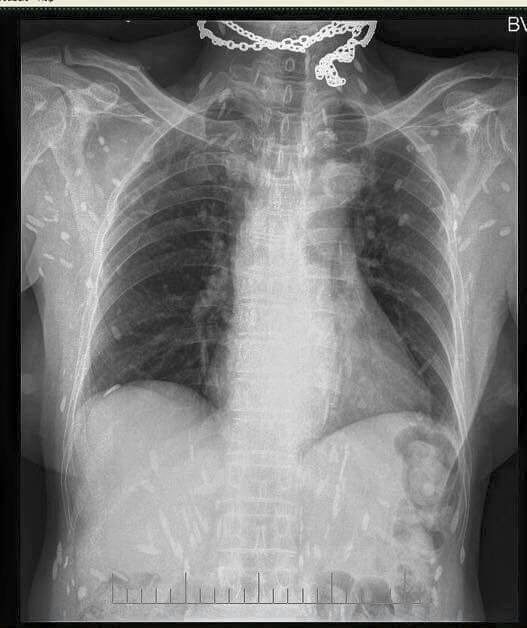

Nếu nhìn hình ảnh chụp phim X-quang của người bị "bệnh gạo" sẽ thấy "gạo" chi chít, rải rác khắp nơi.

Con sán dây, hình ảnh X -quang của người bị mắc X-quang chụp một bệnh nhân bị "gạo" do nhiễm sán lợn.